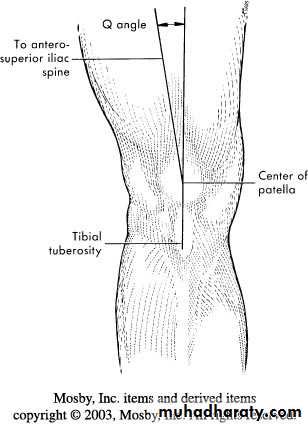

Dislocation of patella

Knee is normally in valgus- quadriceps tend to pull the patella laterally.Sudden severe quadriceps contraction with the knee stretched in valgus lead to lateral dislocation of the patella.

Recurrent dislocation occur in patients with small high patella and excessive genu valgum and joint laxity